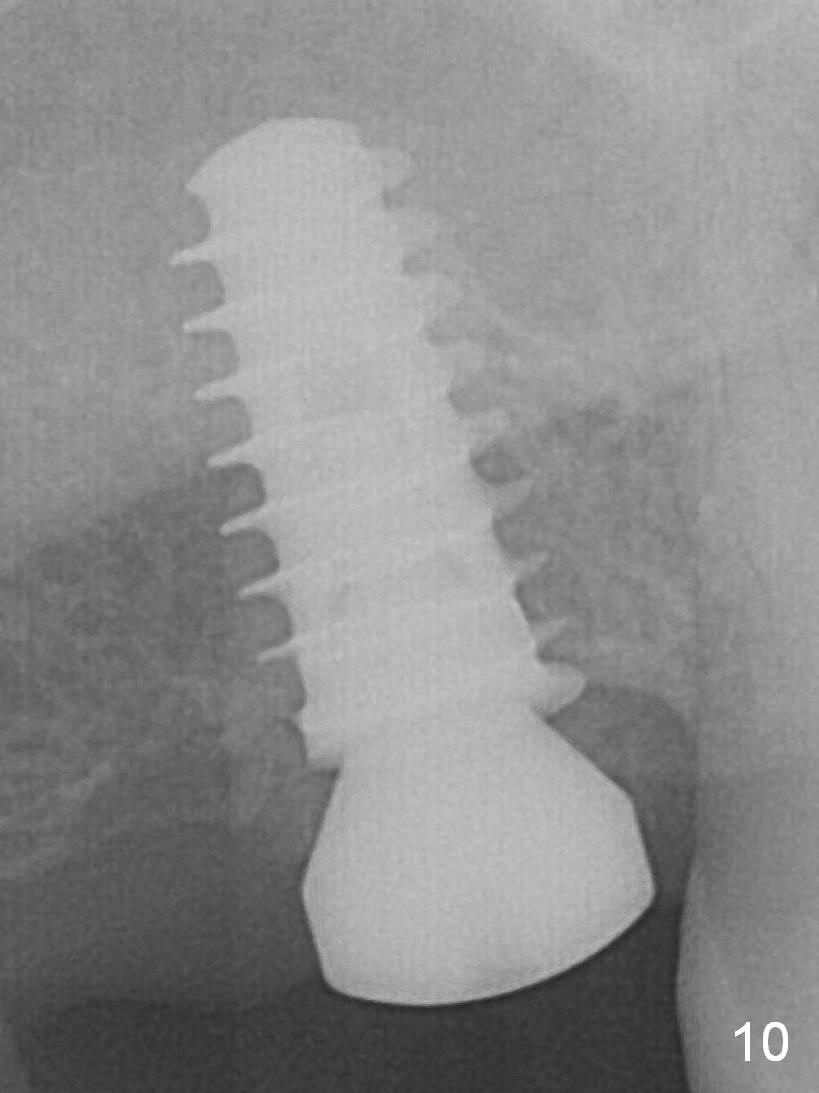

Five months post op, the healing abutment has mobility with light tenderness. The space between the bone and implant is larger than normal (Fig.10). The implant is stable with the healing screw 8 months postop (Fig.11). There is definitive sign of osteointegration 12 months postop (3 months post cementation, Fig.12). The final pair abutment is 5x4(4) mm. The patient is pleased to have the implant for 1 year 7.5 months post cementation (Fig.13).